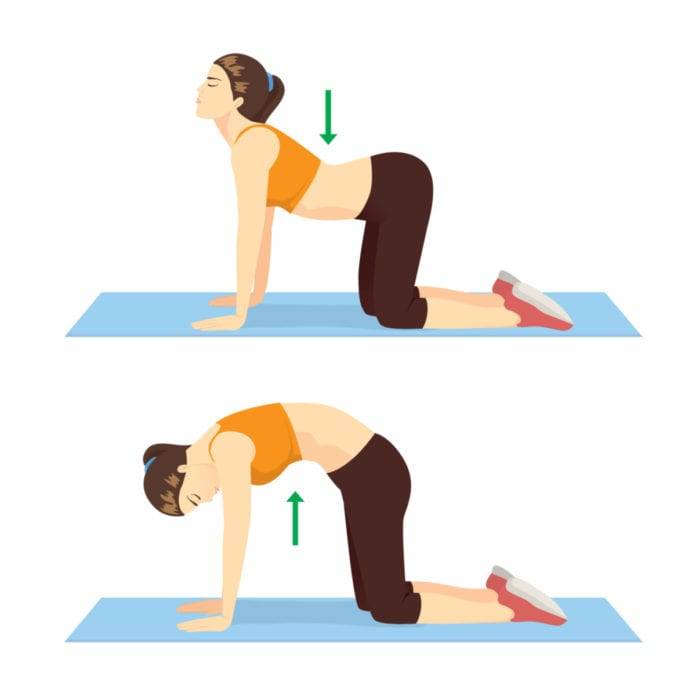

حرکت گربه-گاو

یکی دیگر از انواع ورزش برای صافشدن ستون فقرات حرکت گربه گاو است که طبق مراحل زیر انجام میشود.

- به روی دستها و زانوهای خود قرار بگیرید.

- شکمتان را به سمت ستون فقرات کشیده تا در قسمت کمر کشیدگی ایجاد شده و حالتی گردماننده در پشتتان ایجاد شود.

- چند ثانیه در همین وضعیت بمانید و سپس سر، سینه و دنبالچه را بکشید تا قوسی در کمر ظاهر شود.